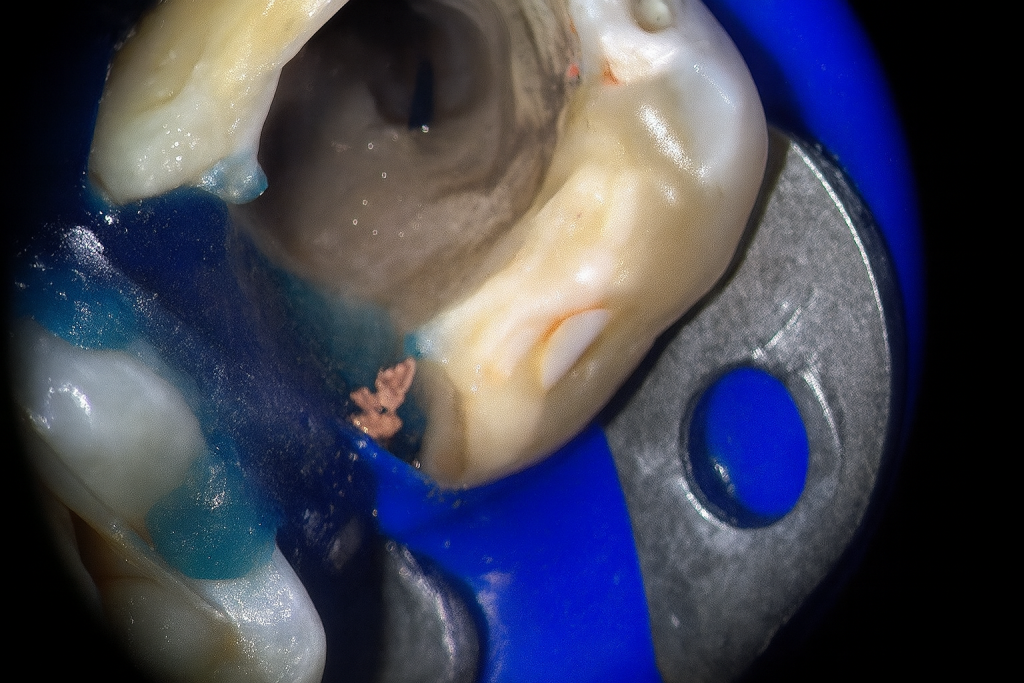

Rubber-dam isolation achieved. Conservative access refined under a dental microscope (Fig 2). The broken instrument was visualized in the coronal third of the distal canal. Ultrasonic tips (ET18D and ProUltra Endo) were used to trephine dentin around the fragment and safely dislodge it.

- Fig 2: Microscopic access and visualization of fractured instrument.